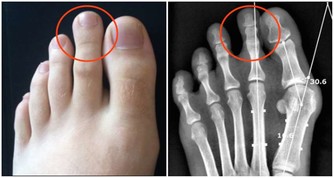

夏天雨水多,且多陣雨、暴雨,如果不能很好的防護躲避,硬冒雨涉水前行並滯留時間過長,很容易使得寒濕之氣進入人體,損傷陽氣,而患發熱、腹瀉、嘔吐等疾患,同時也為風濕性關節炎、類風濕性關節炎等疾病埋下病根。